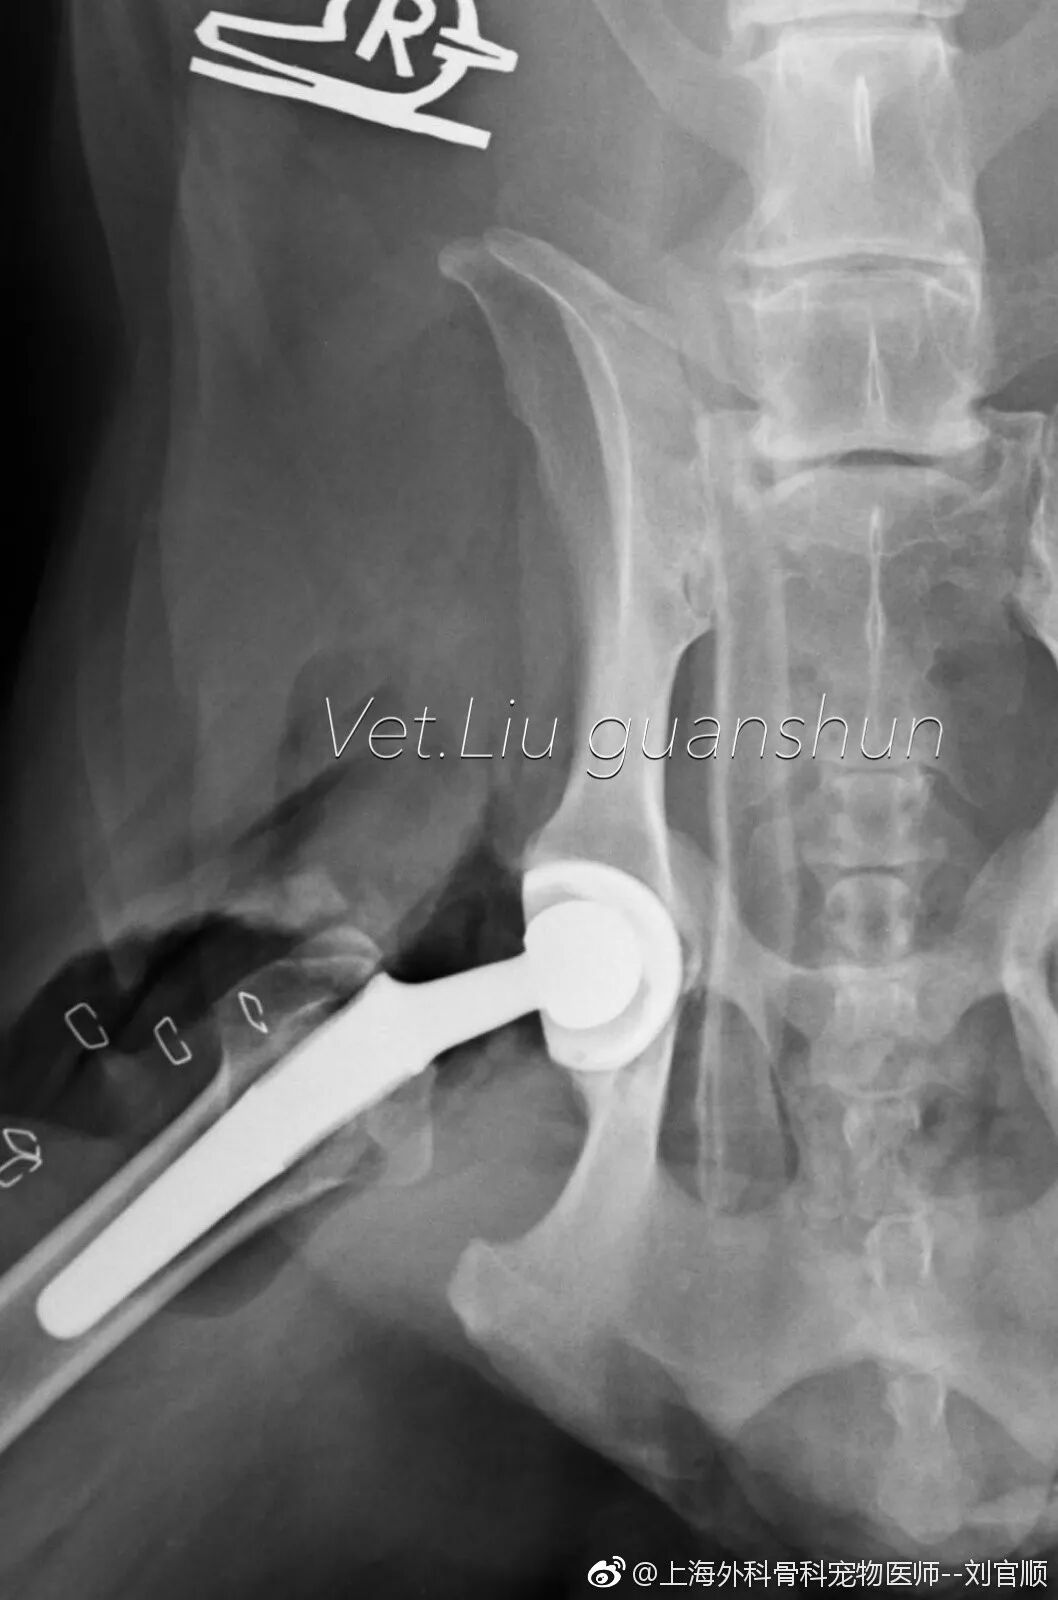

外科专科、骨科专科、心脏病门诊、髋关节置换、前十字韧带手术等

髋关节置换手术后第三天,出来活动活动!

中国取得BioMedtrix全髋置换全部认证的只有两位兽医师